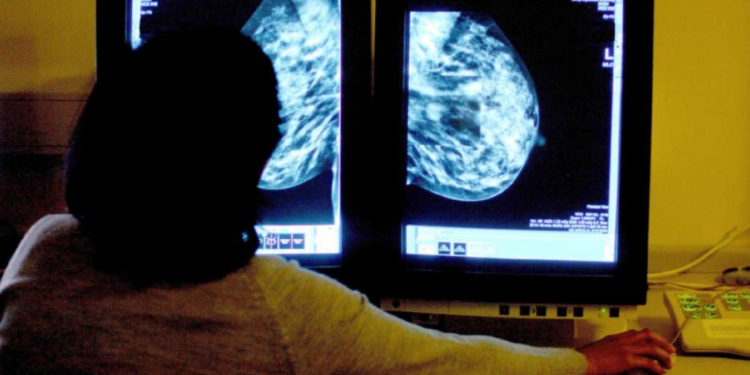

A study conducted by the University of Surrey has identified what it describes as “critical gaps” in breast cancer care for the Black community.

The research found that Black African and Caribbean women in the UK face barriers to accessing screenings, putting them at a higher risk of dying from breast cancer.

In response, the NHS announced the launch of its first national breast screening campaign aimed at addressing these concerns and reaching women from ethnic backgrounds who are less likely to attend screenings.